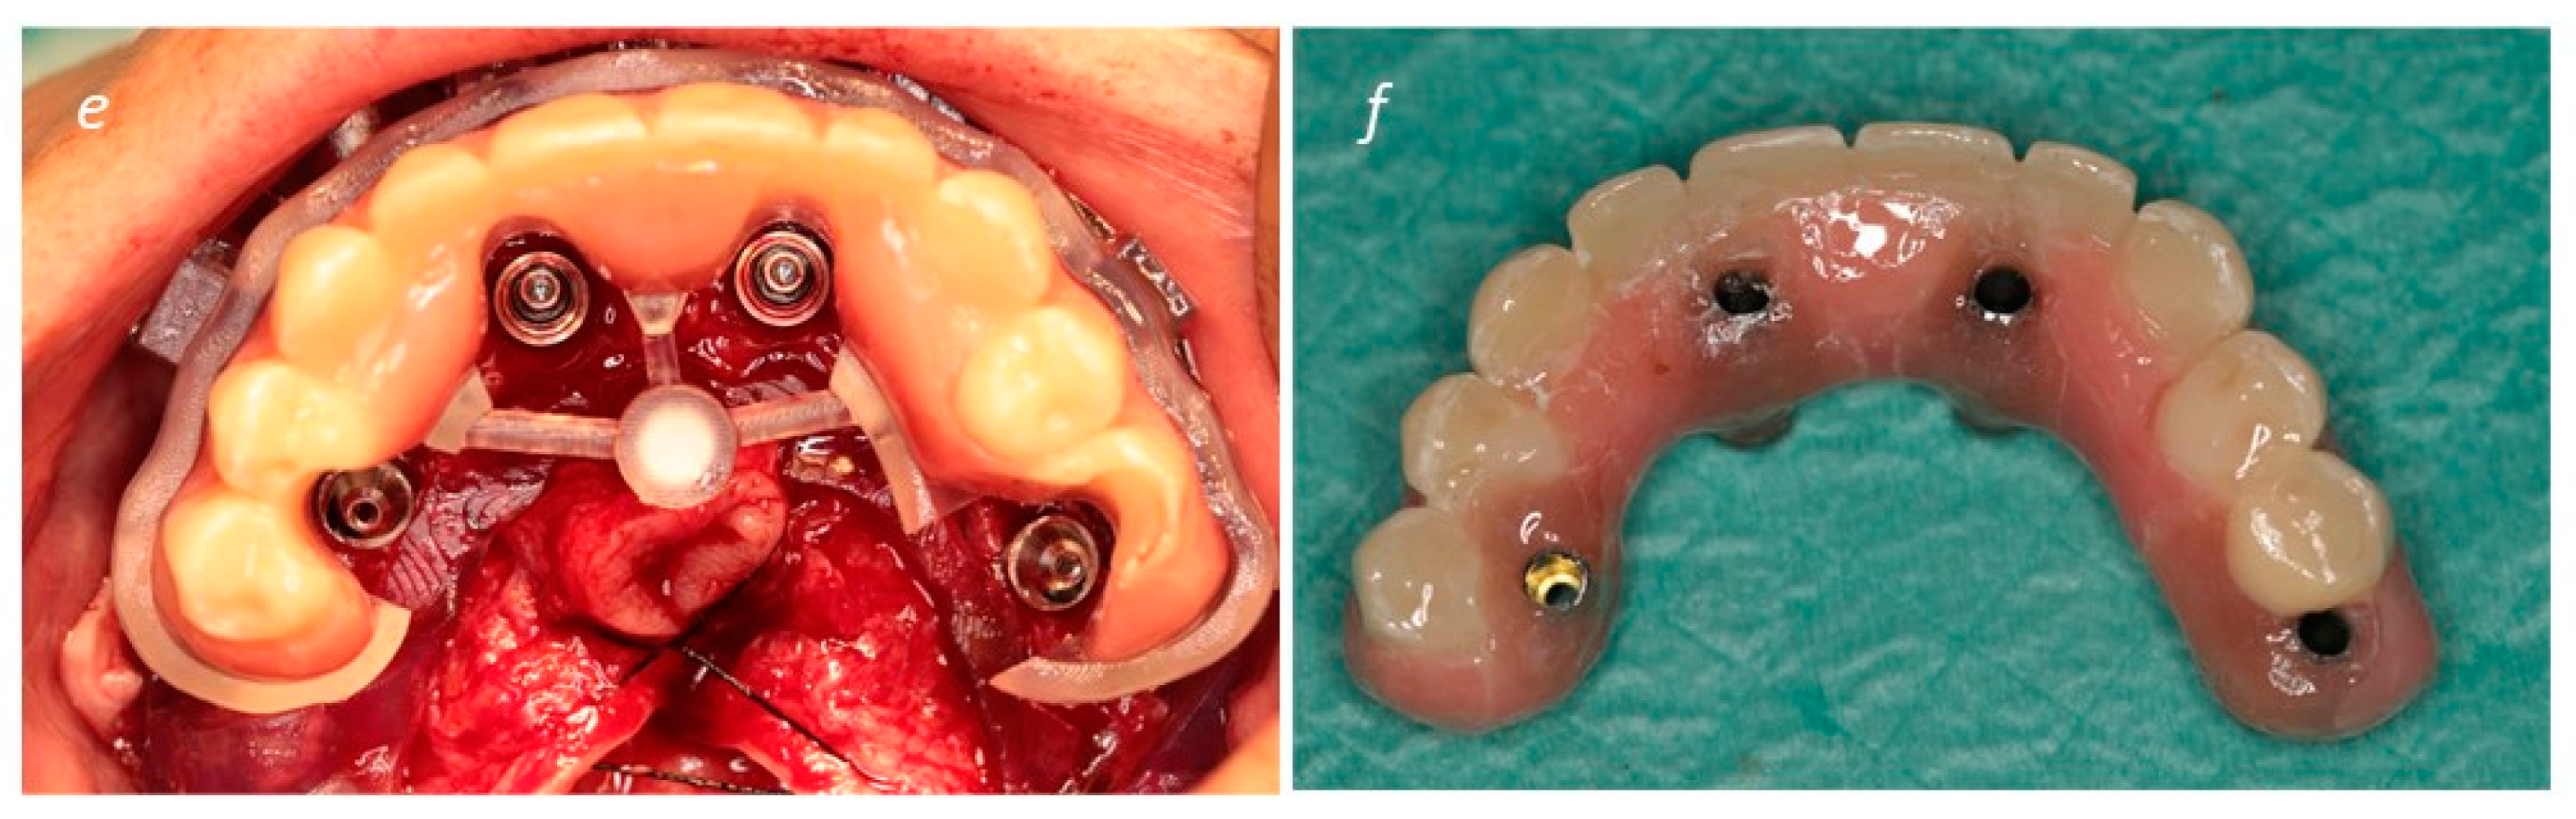

2. Materials and Methods

Description of the Technique

3. Results